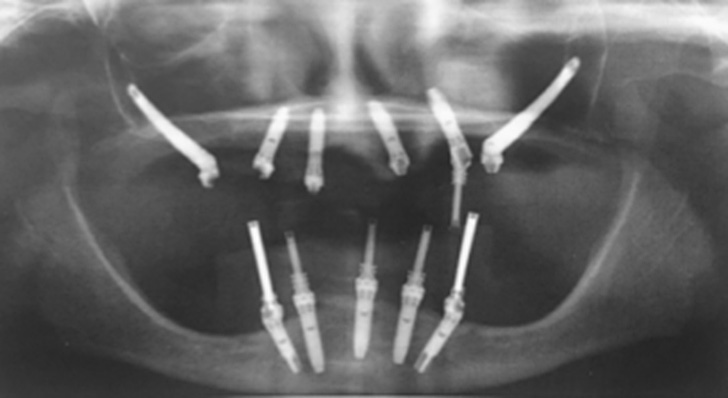

What are zygomatic implants?

Are they different from standart implants?

Yes, zygomatic implants are different from standart. They are longer than and have an inclination that can range from 0 ° to 60 °.

Therefore, computed tomography and orthopantomography are required, which can allow us to assess the position of your anatomical structures. The case will then be examined and a decision will be made on which method to choose.